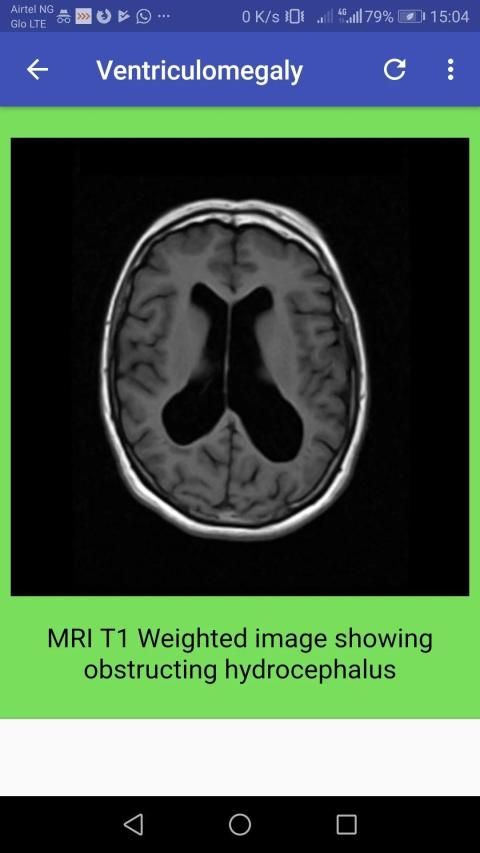

The CT head scan is one of the most common imaging studies that you can be faced with and the most frequently requested by A&E. This app will cover some of the underlying principles of CT head studies, and discuss a method for their interpretation.